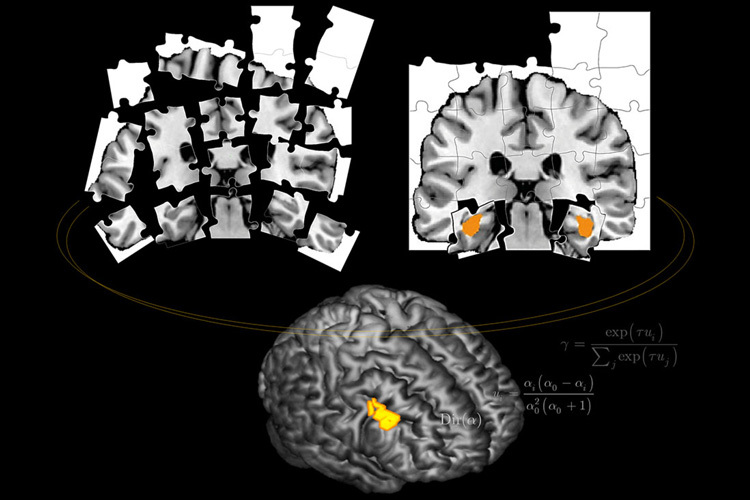

Что именно увидели ученые на томограммах испытуемых? Прежде всего, они обнаружили область мозга, которая — ни много не мало — отслеживает предсказуемость происходящего. Типичная ее реакция — то самое «все страньше и страньше» из «Алисы в Стране чудес».

Эта область — вентролатеральная префронтальная кора — была тем активнее, чем менее определенными были причинно-следственные связи между картинками и результатами игры. Иногда эта область начинала работать согласованно с другой частью мозга, гиппокампом. Гиппокамп — структура, отвечающая за эпизодическую память (то есть память, которая касается происходивших лично с нами событий, а не абстрактных фактов вроде того, что Волга впадает в Каспийское море). Именно эта часть мозга испытуемых становилась активной во время моментального обучения, когда они с одного раза делали вывод о связи картинки и итога игры. При этом гиппокамп в такие моменты работал согласованно с вентролатеральной префронтальной корой, как бы откликаясь на ее «все страньше и страньше».

А во время обычного обучения, когда результаты игры соответствовали ожиданиям, вентролатеральная префронтальная кора и гиппокамп работали вразнобой.